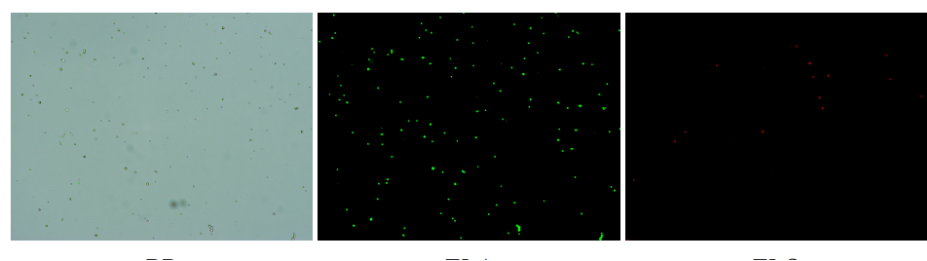

人膽管癌樣本,活性90.45%,結(jié)團(tuán)率7.2%